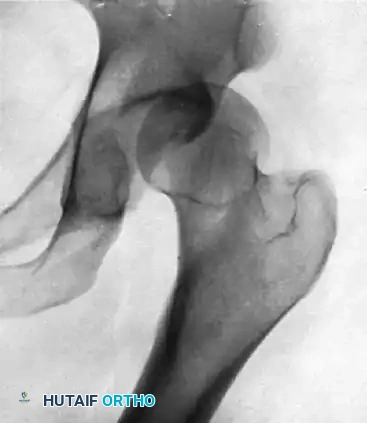

Below is a classic radiographic progression demonstrating the severe sequelae of a posterior hip dislocation:

FIGURE A: Initial anteroposterior radiograph demonstrating a posterior dislocation of the hip. Note the superior and lateral displacement of the femoral head relative to the acetabulum.

FIGURE B: Radiograph taken 8 months after successful closed reduction. The image reveals advanced osteonecrosis of the femoral head. Note the profound subchondral sclerosis, narrowed joint space, and early structural collapse of the femoral head.